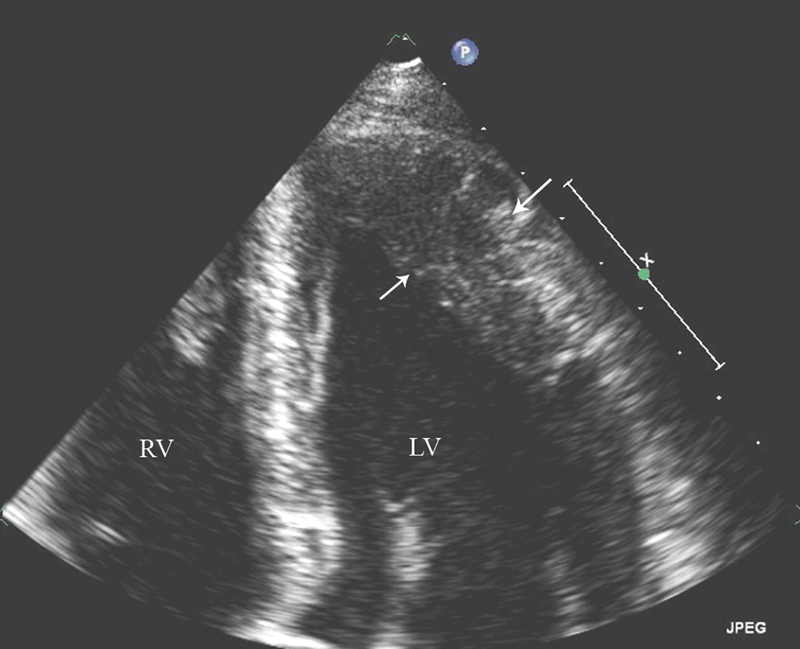

فحوصات تشخيصية لبعض امراض القلب والشرايين التاجية